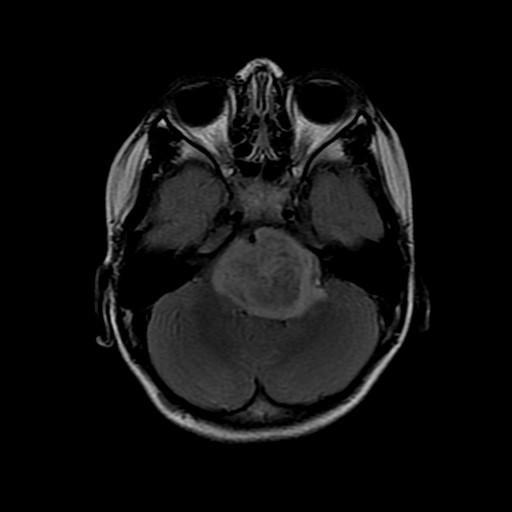

New research conducted in mice provides evidence that highly lethal brain tumors, called high-grade gliomas, stop growing when deprived of a specific molecule naturally produced when brain cells fire. The experiments, led by a group of scientists from Stanford University, Palo Alto, California, suggest that targeting a protein called neuroligin-3 may prove beneficial in patients with these diseases. The work was published in Nature and supported by the National Institute of Neurological Disorders and Stroke (NINDS), part of the National Institutes of Health.

High-grade gliomas cause more deaths than any other form of brain cancer, partly due to the extreme difficulty surgeons have in removing all of the tumor cells. This leaves clinicians dependent on traditional chemotherapy and radiation treatments that have limited success. Depending on the specific subtype of tumor, more than three-quarters of patients die within five years, and for the most common childhood glioma that number exceeds 99 percent.

In the current study, the researchers extracted tumor cells from patients with several varieties of high-grade gliomas and inserted them into the brains of two breeds of mice, one normal and one lacking the gene that produces neuroligin-3. In the latter, none of the tumors grew substantially for four and a half months and roughly half remained stagnant after six months, whereas tumors grew markedly in the mice with an intact neuroligin-3 gene. Further experiments suggested neuroligin-3 triggers a series of chemical reactions that stimulates multiple signaling pathways involved in glioma growth, causing the tumors to expand.